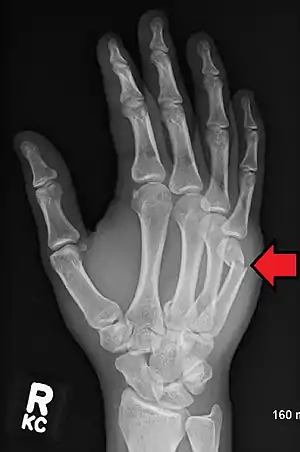

A boxer's fracture is the break of the 5th metacarpal bones of the hand near the knuckle.[4] Occasionally it is used to refer to fractures of the 4th metacarpal as well.[1] Symptoms include pain and a depressed knuckle.[2]

| Boxer's fracture of the 5th metacarpal head from punching a wall | |

Classically, it occurs after a person hits an object with a closed fist.[3] The knuckle is then bent towards the palm of the hand.[3] Diagnosis is generally suspected based on symptoms and confirmed with X-rays.[3]

Diagnosis by a doctor’s examination is the most common, often confirmed by x-rays. X-ray is used to display the fracture and the angulations of the fracture. A CT scan may be done in very rare cases to provide a more detailed picture.